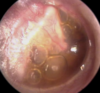

*He has post-auricular inflammation and his right tympanic membrane looks opaque and inflamed* Dx? [1] Tx? [1]

**Mastoiditis** is a medical emergency due to the potential risk of **meningitis** - Refer urgently to AE